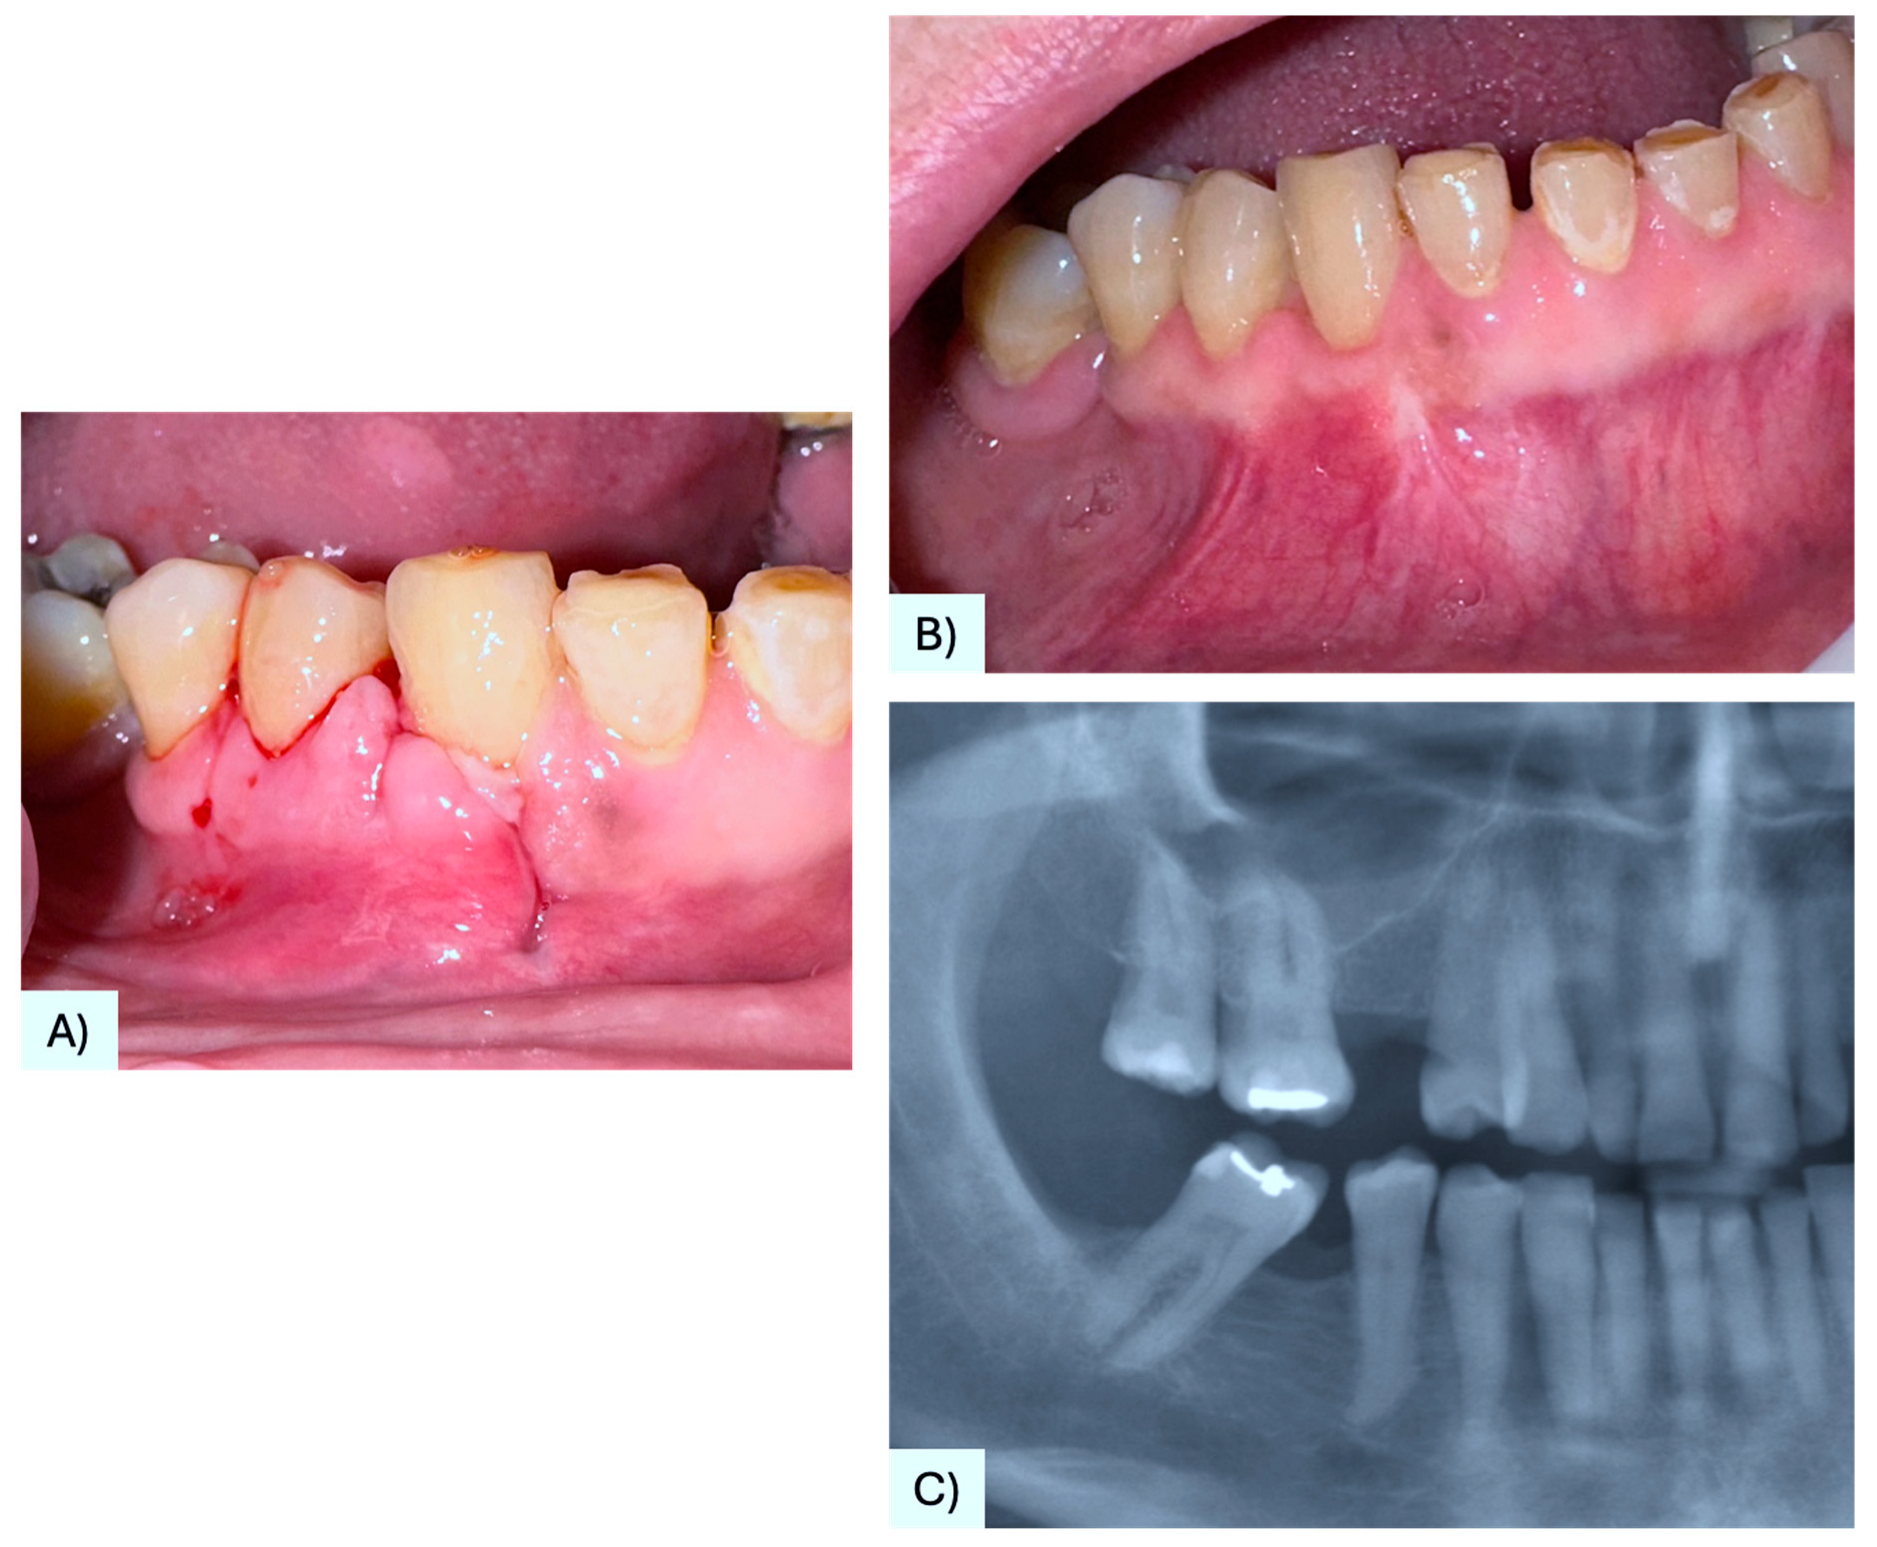

| 32 | Lado Lako Loro et al. [25] | 71 M | Maxilla, gingiva between #1.3, #1.4 | Asymptomatic nodule | 10 mm | Radiolucency with a defined margin area | Alveolar bone resorption | Excision, curettage | No evidence after 10 months | 2023 |